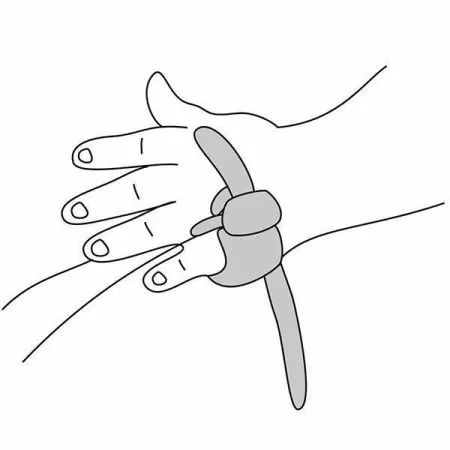

- Датчик пульсоксиметрический «Манжетка» состоит из Y-образной пары излучатель-фотоприемник и фиксирующего ремешка. Поместите излучатель и фотоприемник в разъемы фиксирующего ремешка и закрепите на пациенте.

- При этом следует следить, чтобы излучатель находился напротив фотоприемника и фотоприемник прилегал к мягким тканям.

- Не затягивайте датчик слишком сильно, чтобы не нарушить циркуляцию крови.